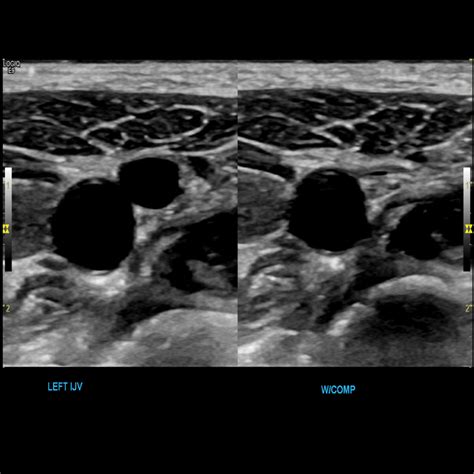

• Doppler Ultrasound: This non-invasive test uses sound waves to create images of the veins and assess blood flow. It can help identify blockages, clots, and other abnormalities.

• upper extremity veins ultrasound